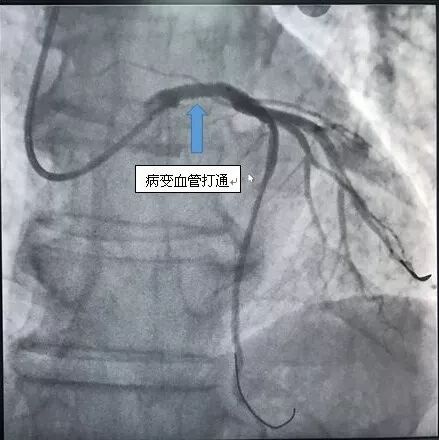

下午4点手术开始,造影显示李爹爹左主干严重狭窄 90%以上,命悬一线。在向病人家属交代病情后,王祥教授带领黄仲略主任和苏华俊主任迅速为患者植入支架,打通血管。血管打通仅花了20分钟。